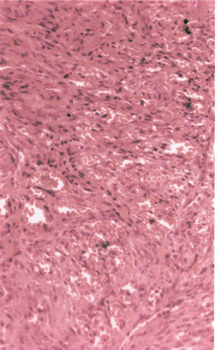

При всех клинических вариантах СК патоморфологическая картина однотипна (см. рис. 36 на цветной вклейке) и характеризуется сочетанием 3 основных признаков:

Рисунок 36. Микропрепарат. Узловой элемент саркомы Капоши. Пролиферация веретенообразных клеток вокруг примитивных сосудистых пространств, окраска гематоксилин-эозин, увеличение 250 раз

— хаотичным незавершенным ангиогенезом,

— пролиферацией веретенообразных клеток с маркерными признаками эндотелия,

— иммунноклеточной монононуклеарной инфильтрацией.

Для типичных случаев CК не характерны полиморфизм и высокая митотическая активность веретенообразных клеток. Вместе с тем иногда при гистологическом исследовании можно отметить признаки более высокой «агрессивности» опухоли в виде значительной атипии и полиморфизма ядер веретенообразных клеток, большего количества фигур митоза. Особенно часто такие изменения регистрируются при эндемической CК. При CК, ассоциированной со СПИДом, описаны изменения, которые трудно отличить от ангиосаркомы.